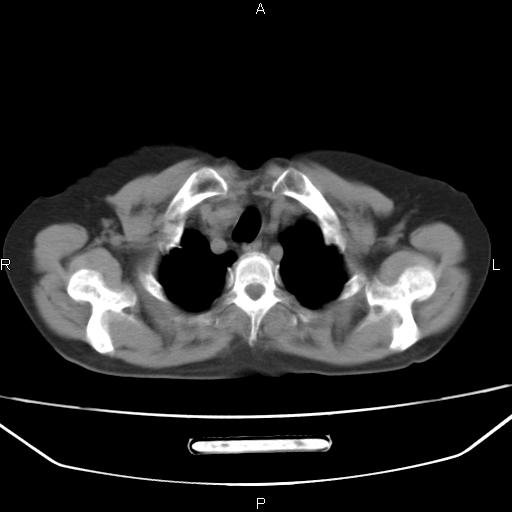

患者,女,66岁。健康体检胸部透视发现右上肺片状阴影。既往无不适,患者自诉三个月前曾有低热病史体温37.5左右一周。用药后缓解。至今无其它不适。请老师们指导指导。

考虑:右肺上叶周围型肺癌(分叶状肿块+砂粒状钙化+胸膜尾征)。

病灶见明显分叶、大小较大(大于3cm?),老年人,多考虑:肺癌,建议穿刺活检。

典型的中心型肺癌,尖段支气管阻塞。

以下是引用dyqct在2010-6-3 9:32:00的发言:[br]考虑:右肺上叶周围型肺癌(分叶状肿块+砂粒状钙化+胸膜尾征)。

不像中央型啊

右肺上叶周围型肺癌可能性大。

考虑:右肺上叶周围型肺癌